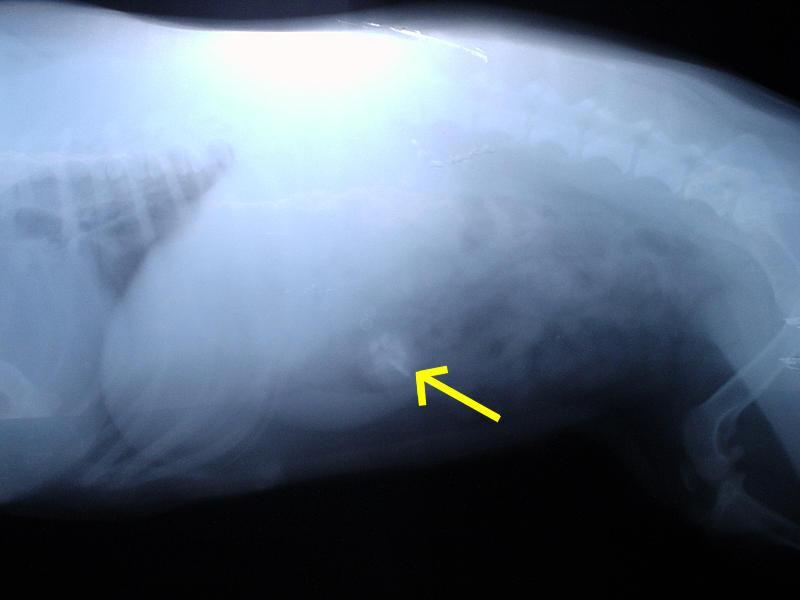

Foto: Cizí tělesa v zažívacím traktu a kostní trus.

Fotogalerie > PSÍ SVĚT: Veterinární poradna > Cizí tělesa v zažívacím traktu a kostní trus.